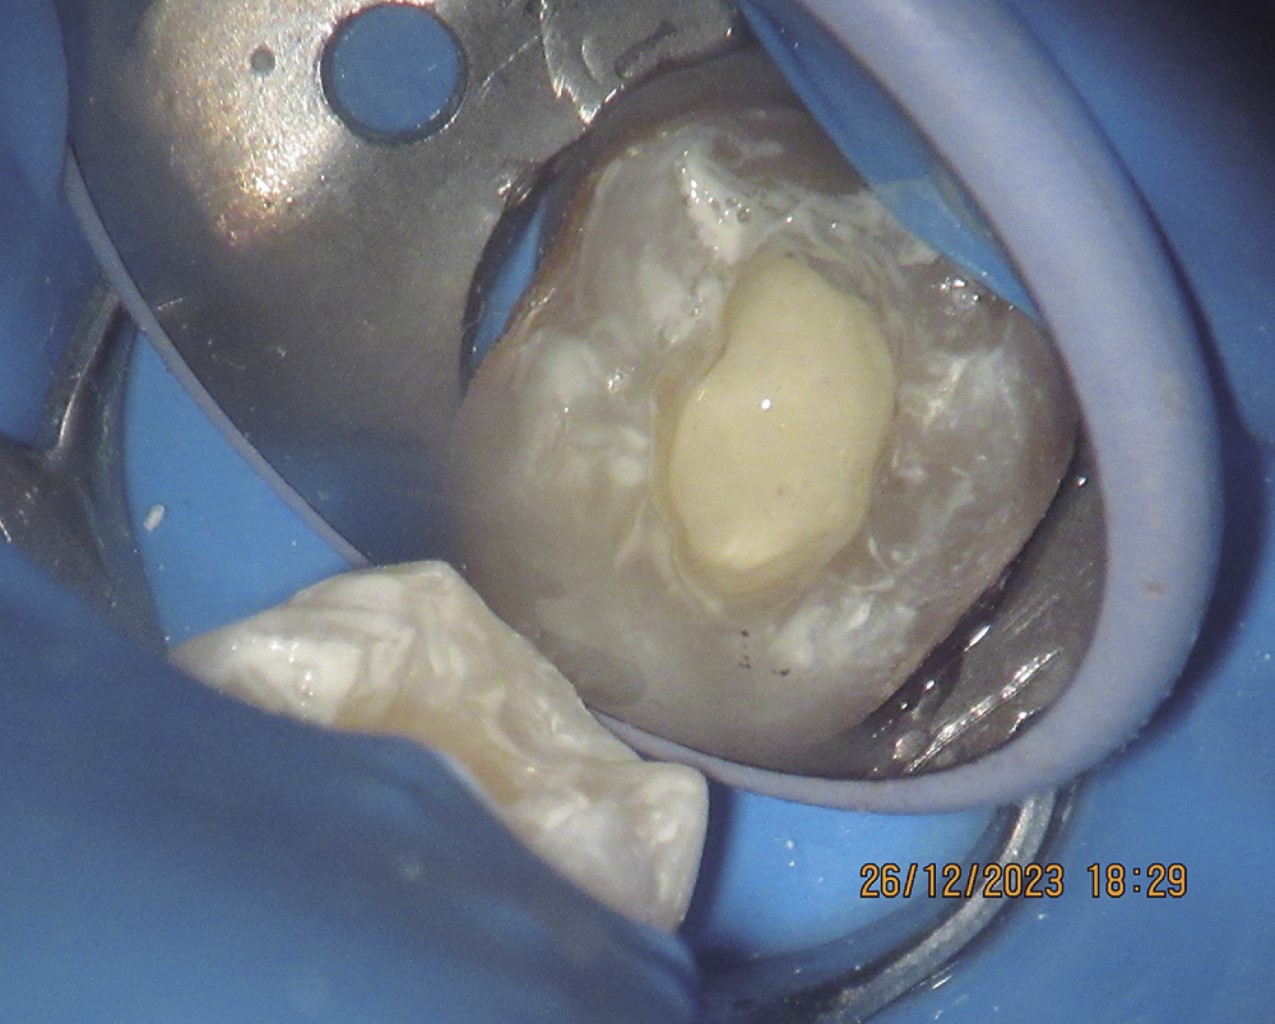

Con esta información establecimos el siguiente plan de tratamiento: se inicia endodoncia convencional en la raíz mesial, bajo anestesia local con lidocaína al 2% (Zeyco, México) y aislamiento absoluto con dique de goma (Nictone, México), se instrumentan dos conductos radiculares con el sistema rotatorio G Super Blue (DreamSpace, China), irrigando entre cada lima con hipoclorito de sodio al 5.25%, una vez terminada la instrumentación, se hace irrigación ultrasónica pasiva con tres ciclos de 20 segundos en cada conducto, usando un equipo de ultrasonido inalámbrico Endo Ultra Activator (DreamSpace, China), seguido de esto se irriga con solución EDTA al 17% (Viarden, México) usando 5 mL y dejando la solución durante 3 minutos dentro del conducto, para luego terminar la irrigación con agua destilada 10 mL durante 3 minutos más (Figura 10).

Terminado lo anterior, se secan ambos conductos con puntas de papel 35/04 (Gapadent, China), para la obturación se utilizó cemento sellador para canales radiculares Sealapex (Kerr Endodontics, Italia) y puntas de gutapercha F3 (Dentsply Sirona, India) (Figura 11).

Para el tratamiento de la raíz distal, al presentar una gran amplitud, solamente se hizo una ligera instrumentación con lima tipo K calibre 60 (Dentsply, México) para remover los restos de tejido presentes en el conducto, se irrigó con solución fisiológica 5 mL a muy baja presión durante 3 minutos, el conducto se secó después con puntas de papel calibre 70 (Gapadent, China), se decidió obturar de forma completa el canal distal con biodentine (Septodont, Francia), para lo cual se controló el nivel de obturación bajo microscopio dental, tomando en cuenta la longitud obtenida en la tomografía, una vez obturado el conducto distal, se colocó el resto del biodentine de forma uniforme sobre el piso de la cámara pulpar hasta aproximadamente la mitad de la misma, esto con objeto de mantener un grosor de material suficiente y prevenir que con el paso del tiempo hubiera comunicación hacia el conducto radicular por reabsorción del biodentine (Figuras 12 y 13).

Figura 10

Figura 11

Figura 12

Figura 13